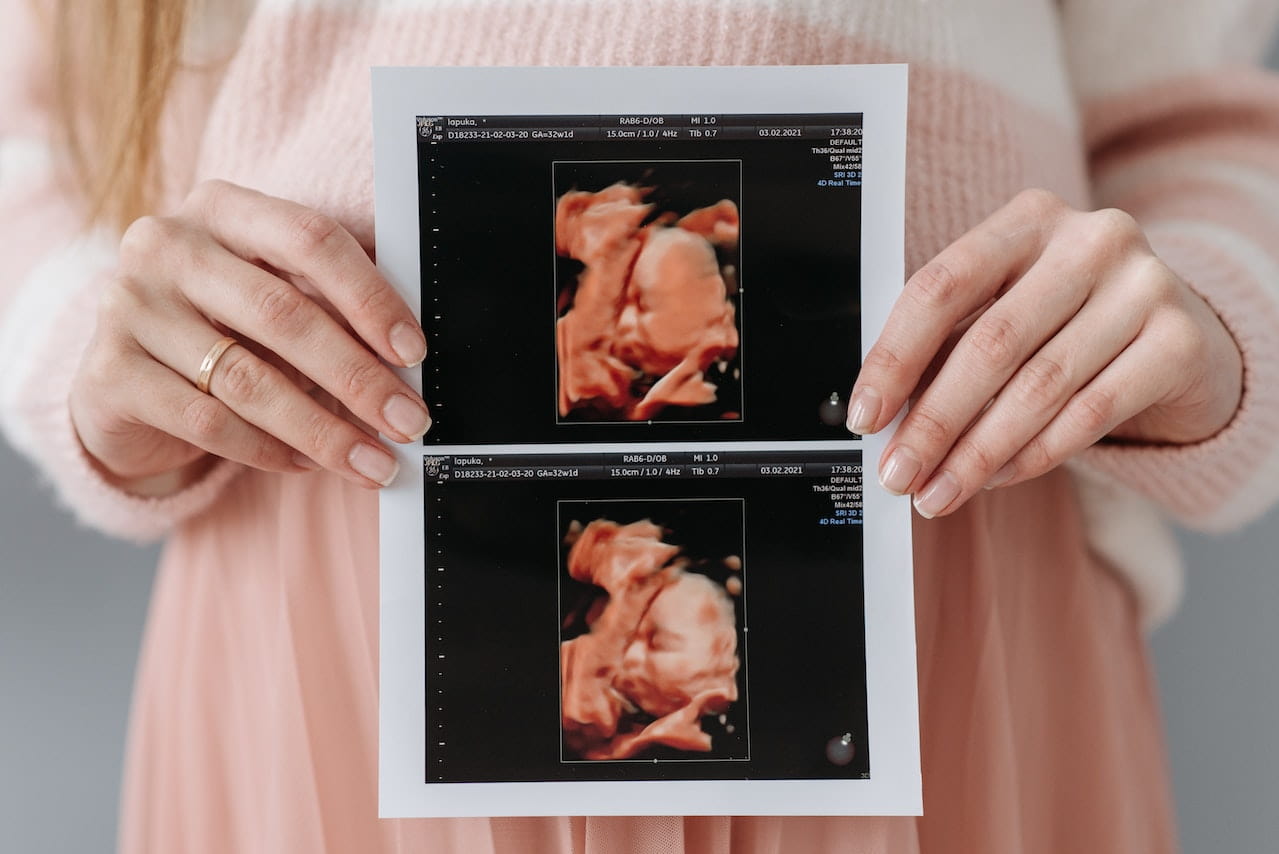

این نوع سونوگرافی معمولا در سه ماهه دوم و بین هفته های 18 تا 22 بارداری انجام می شود. همانطور که از نام آن پیداست، هدف آن بررسی آناتومی نوزاد است. همچنین به تعیین سن حاملگی، تعداد جنین ها و همچنین محل جفت کمک می کند. متخصص سونوگرافی اندازه گیری های زیادی را از نوزاد انجام می دهد تا هر گونه ناهنجاری را تشخیص دهد. تصاویری برای بررسی رشد مغز، صورت، قلب، ستون فقرات، قفسه سینه، پاها، دستها و اندامهای اصلی نوزاد گرفته میشود. محل جفت و عروق در بند ناف نیز بررسی خواهد شد. مقدار مایع اطراف نوزاد اندازه گیری می شود و دهانه رحم، رحم، تخمدان ها و مثانه برای هر گونه ناهنجاری بررسی می شود. اگر در معرض خطر بالای ناهنجاری های جنینی هستید، سونوگرافی آناتومیک ممکن است در اوایل بارداری (بین هفته های 11 تا 16) انجام شود. شما حق دارید در صورت مشخص شدن جنسیت نوزاد در سونوگرافی بپرسید.

سونوگرافی سه ماهه دوم بارداری

این سونوگرافی معمولا بین هفته 18 تا 22 بارداری پیشنهاد می شود. هدف اصلی آن دیدن بیشتر اندامها و اندامهای کودک شما (قلب، کبد، کلیهها، معده، مثانه، مغز و غیره) برای تشخیص ناهنجاریها و مداخله در صورت لزوم است. همچنین امکان بررسی: